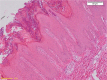

Psoriasiform dermatoses represent a wide spectrum of inflammatory conditions, with several major forms represented by psoriasis, as the prototype of this category, followed by pustular psoriasis, Reiter's syndrome, pityriasis rubra pilaris, lichen simplex chronicus and large-plaques parapsoriasis. They create a diagnostic challenge, both clinical and histopathological, because of their complexity and frequent overlapping of the microscopical features. The characteristic histopathological features of psoriasiform reaction comprise extensive hyperkeratosis, with horizontally confluent but vertically intermittent parakeratosis, which alternate with orthokeratosis, thin granular layer, with relative frequent mitoses, uniform elongated and fused rete ridges, edematous superficial papillary dermis, with dilated capillaries, perivascular lymphocytic infiltrate, Munro's microabscesses, and spongiform pustules of Kogoj. Our paper aims to review the histopathology of major form of psoriasiform dermatoses and to emphasize the characteristic microscopical differences between them, for a better approach of the diagnosis as an important key for clinical and therapeutical management. Using the clinicopathological correlations, a thoroughly evaluation of the microscopical features and compartments distribution or special stainings and techniques, the range of differential diagnosis can be decreased and a more accurate diagnostic can be usually achieved. The insights into the pathogenic mechanisms can lead to new therapeutic opportunities targeted to the specific type of inflammatory lesion.